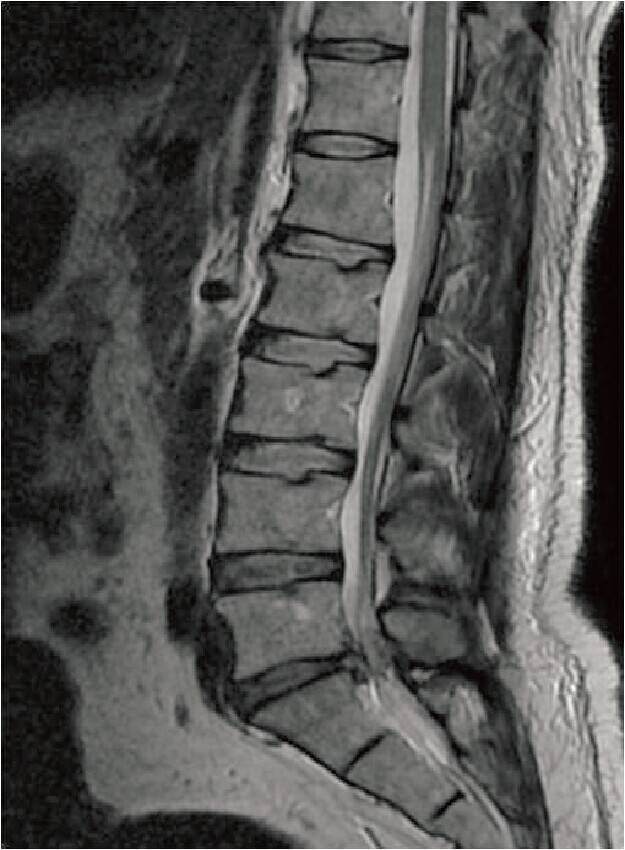

诊断:椎间盘突出症(L5〜S1)。

下图为:术后7天MRI L5~S1突出椎间盘被摘除